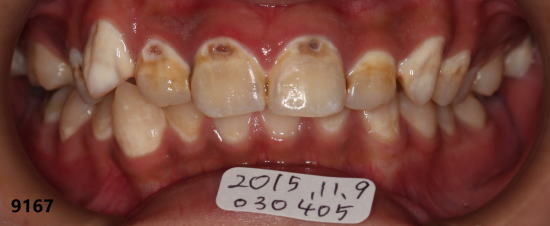

| 2015年12月14日:フッ素洗口開始して約4ヶ月半後 |

矢印の部分のむし歯(白濁)がなくなり、むし歯が消失(再石灰化)して きているのがわかります。 |